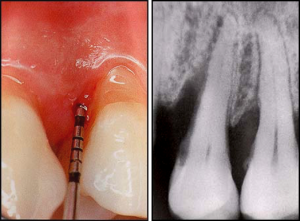

BEFORE

Thorough cleaning of root surfaces beneath the gum line to remove plaque and tartar deposits.